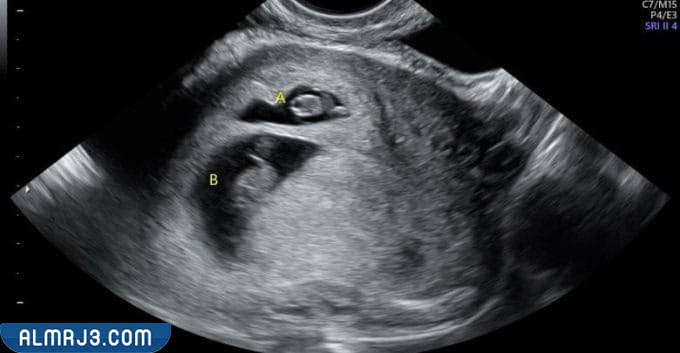

تزداد نسبة هرمون الحمل داخل الغدد التناسلية لجسم المرأة بعد التلقيح وإتمام عملية التصاق البويضة في جدار الرحم، ولكن وبعدما تذهب الأم إلى الطبيب المعالج قد يتعرف على وجود جنين داخل الرحم باستخدام الموجات فوق الصوتية، ويتم ذلك الأمر بعد انتهاء الدورة الشهرية بفترة بسيطة من الوقت قد تصل إلى الأسبوعين أو الثلاثة أسابيع، كذا ويساعد جهاز الدوبلر المخصص للكشف عن نبضات الجنين في توضيح عدد الأجنة الموجودة داخل الرحم وذلك لأنه عند الحمل بتوأم يصدر هذا الجهاز نبضات مزدوجة يستطيع الطبيب المعالج من اكتشافها بمنتهى السهولة.

- نبضات قلب مزدوجة: يبدأ الطبيب في سماع نبضات قلب الجنين للاطمئنان عليه، ولكنه قد يكتشف أن هذه النبضات مزدوجة؛ مما يؤكد وجود جنين آخر داخل الرحم.